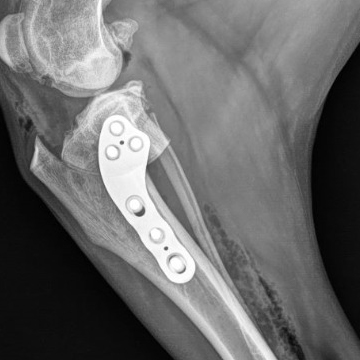

The RITA LEIBINGER Titanium TTA RAPID® Tiny, 2.0/2.4 TPLO and Titanium TPLO Swing, and our 2.0/2.4 Titanium CBLO implant systems and instrumentation are specifically designed for small patients, and can help overcome these challenges. They are typically smaller in size and have different geometries to accommodate the smaller bone structure of small dogs and cats.